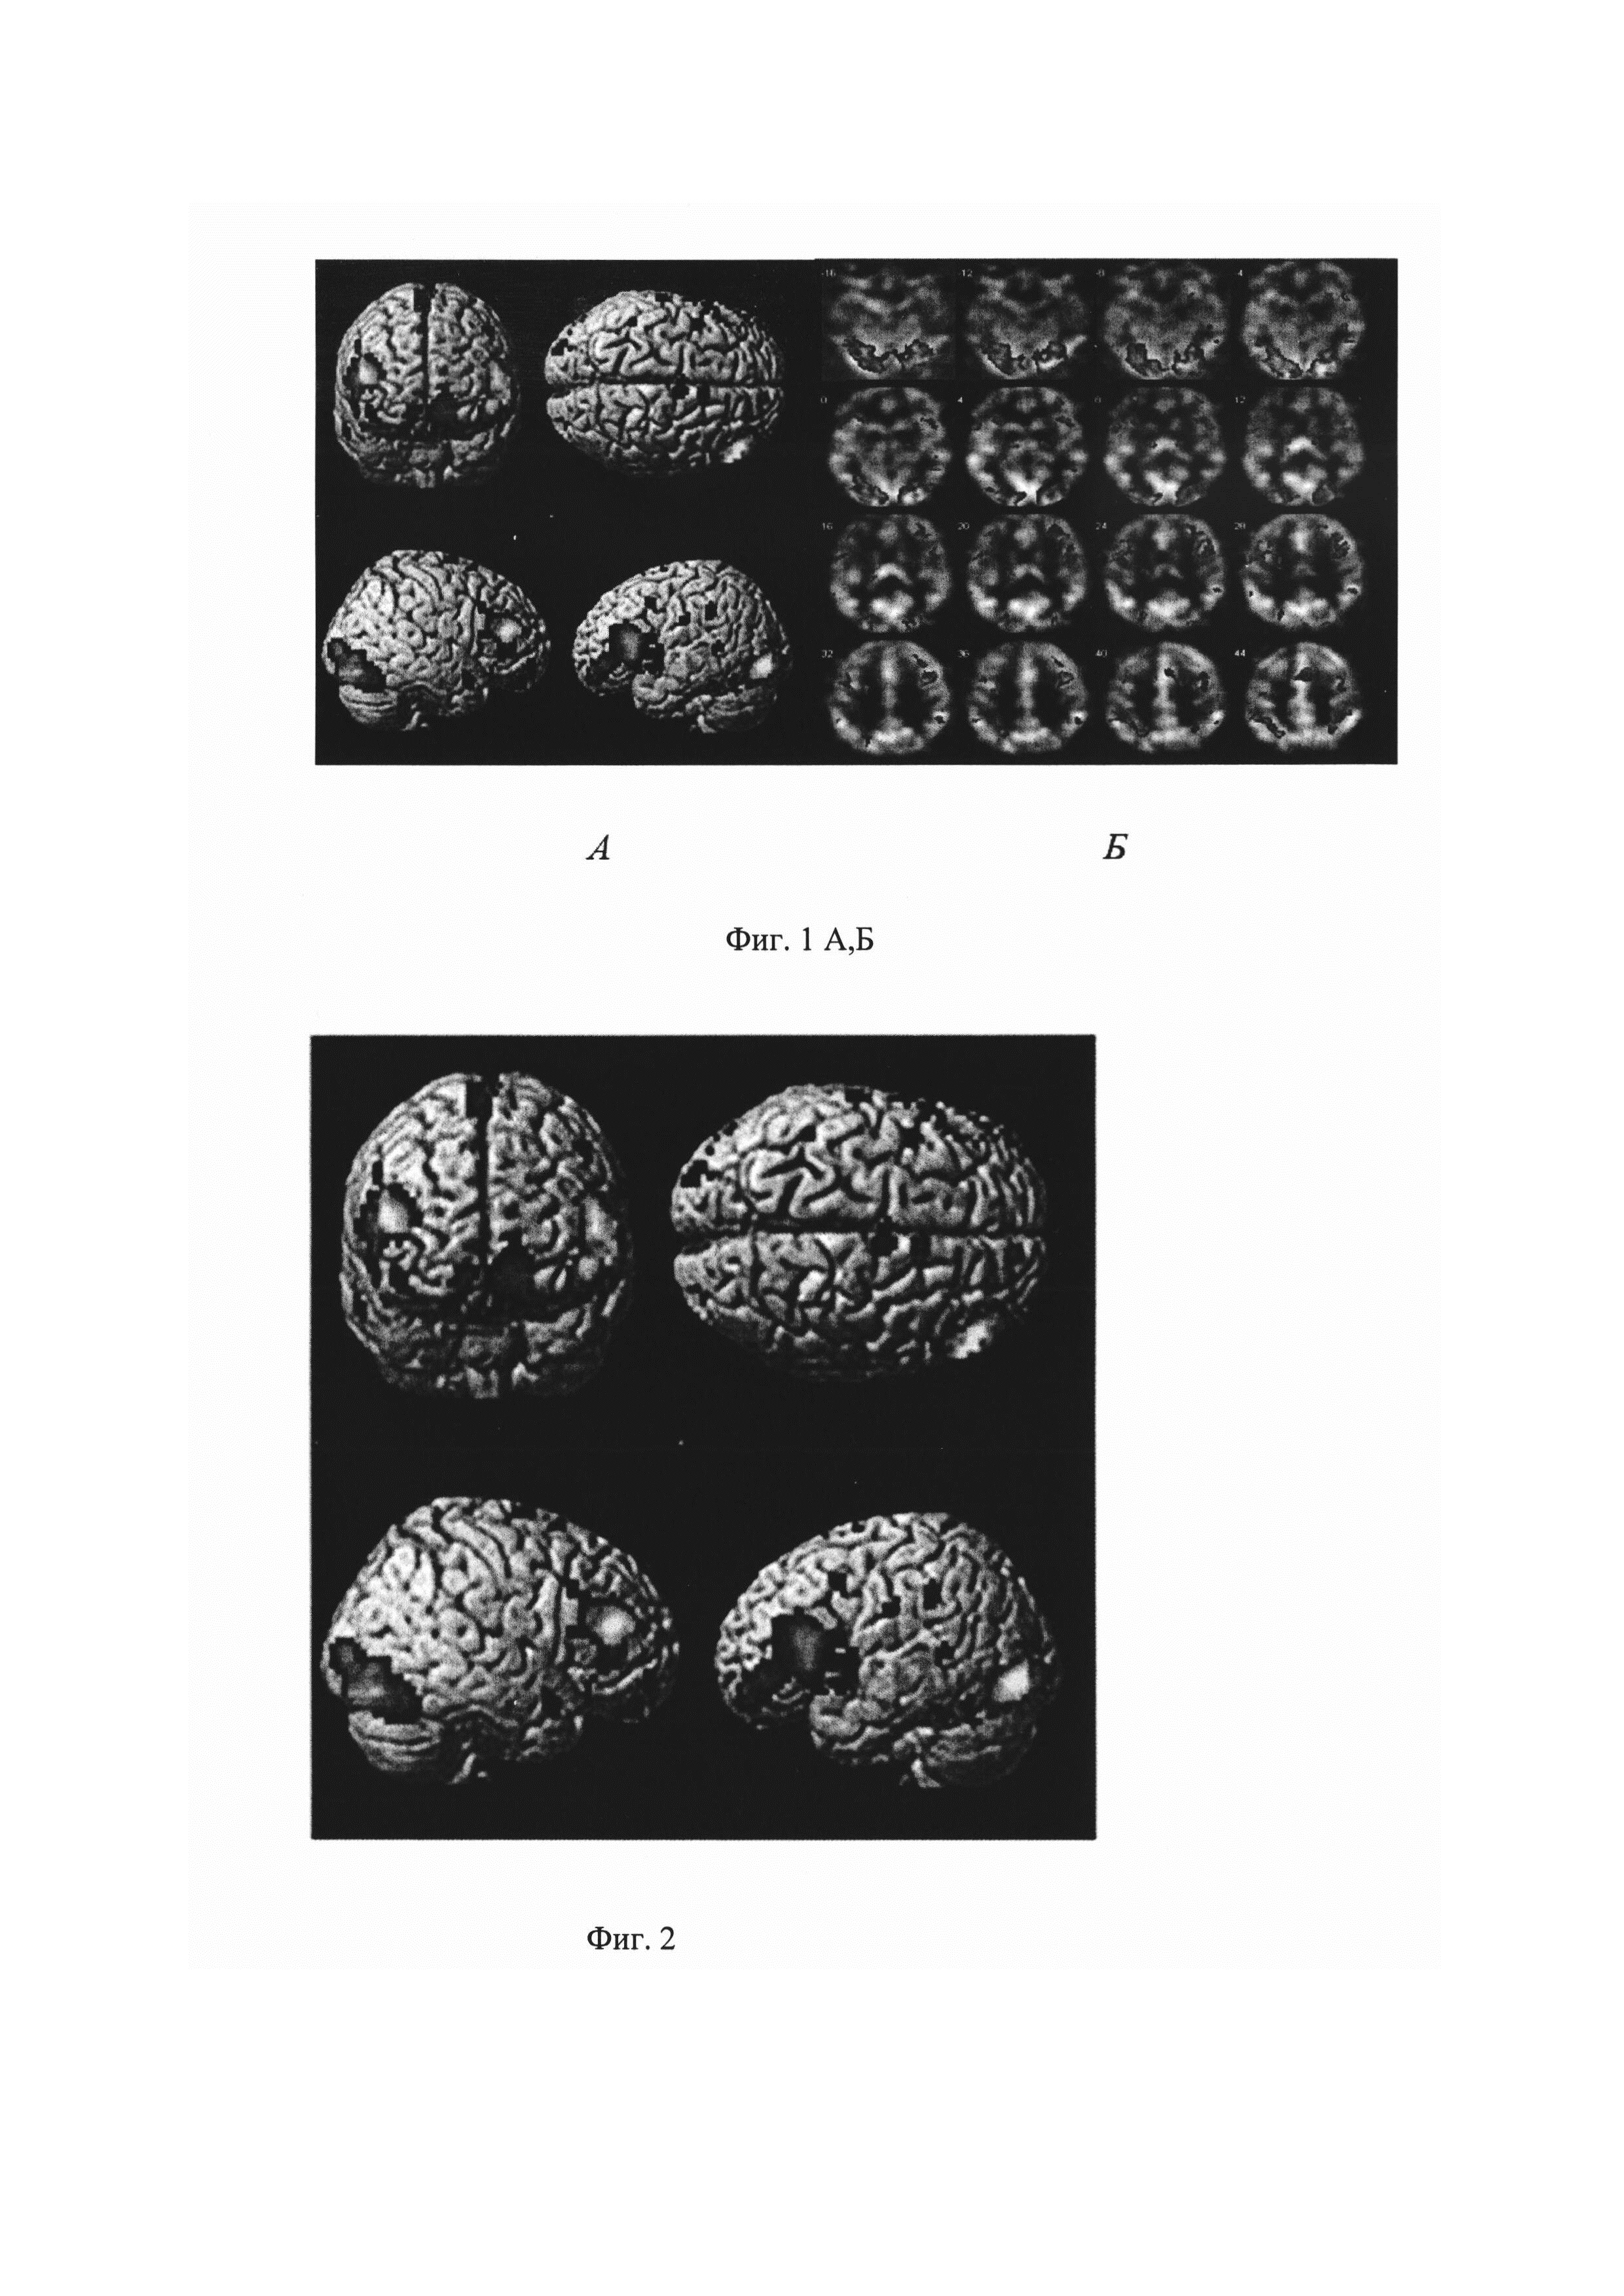

Изобретение относится к области медицины, в частности к неврологии и может быть использовано для оценки параметров тканевого кровотока в зонах нейрональной активации. На сегодняшний день цереброваскулярные заболевания являются одной из важнейших медико-социальных проблем, что обусловлено их высоким процентом в структуре заболеваемости, инвалидизации и смертности (Кардионеврология. Современное состояние и перспективы развития. / З.А. Суслина А.В. Фонякин, Л.А. Гераскина // Сборник статей и тезисов II Национального конгресса «Кардионеврология» / под ред. З.А. Суслиной и др., - М., 2012. - С. 7-13). Возможность нормального функционирования головного мозга без полноценного снабжения его кислородом и другими питательными веществами, невозможна. При нарушении работы сосудов, в том числе и на уровне микрокапилляров, ухудшается кровоснабжение и приток необходимых питательных веществ, начинает развиваться ангиопатия сосудов. Снижение мозговой перфузии является одним из основных факторов в развитии ишемии головного мозга, когнитивных расстройств, формирования инсульта. Поэтому особый интерес вызывает изучение церебральной перфузии с оценкой цереброваскулярного резерва (реактивности), нейроваскулярного взаимодействия, фракции экстракции кислорода у пациентов с микроангиопатией (small vessel disease), а также изучение перфузионных показателей в базовом (покой) и активном (выполнение той или иной парадигмы) состоянии головного мозга. Среди методов оценки кровоснабжения головного мозга одним из наиболее часто применяемых в клинической практике являются перфузионные методы с определением показателей тканевого кровотока. Церебральная перфузия позволяет оценить активность головного мозга и играет ведущую роль в качестве показателя функционирования головного мозга в норме и при патологии. Методы изучения тканевого кровотока чаще всего основываются на оценке изменения концентрации красителя, радиофармпрепарата и контрастного вещества, введенного в сосудистое русло (Сергеева А.Н. Церебральная гемодинамика при стенозирующем поражении внутренних сонных артерий (клинико-кт-перфузионное исследование). Автореферат дисс. на соиск. учен. степ. канд. мед. наук, Москва, 2013, 21 с.). Альтернативой этим методам является бесконтрастная магнитно-резонансная перфузиия - ASL (метод меченых артериальных спинов), не требующая введения контрастного препарата, так как для создания болюса «меченной» артериальной крови применяют эндогенный маркер - маркированные спины, втекающие с артериальной кровью в ткани мозга. В итоге сканирование головного мозга дает серию повторов с усредненным по интенсивности сигналом в каждом вокселе изображения с получением «контрольных» - базовых (без предварительного инвертирования или насыщения спинов молекул воды артериальной крови) и «маркированных» изображений, контрастность которых будет сформирована в присутствии «меченных» спинов. Вычитая контрольное изображение из маркированного, получают срезы с тканевой контрастностью, соответствующей распределению маркированных спинов в ткани мозга, то есть перфузионные изображения. Известен способ оценки скорости церебрального кровотока в зонах нейрональной активации, включающий проведение ряда экспериментов по валидации и стандартизации значений скорости церебрального кровотока (CBF) по сравнению с позитронно-эмиссионной томографией (ПЭТ). У здоровых добровольцев показана высокая корреляция значений CBF, измеренных с помощью ПЭТ и ASL. Метод ASL позволяет оценить значения CBF в любой области коры головного мозга. В результате данного исследования получены абсолютные значения скорости мозгового кровотока в покое, варьирующие в зависимости от выбранной зоны измерения в пределах 56-71 мл/100 г/мин. (Пронин И.Н., Фадеева Л.М., Подопригора А.Е. и др. Спиновое маркирование артериальной крови (ASL) - метод визуализации и оценки мозгового кровотока. Лучевая диагностика и терапия. 2012; 3: 64-78). Однако оценка CBF ограничена в белом веществе головного мозга из-за низкой скорости кровотока в нем, приводящей к редукции и искажению ASL сигнала (van Gelderen Р, de Zwart JA and Duyn JH. Pittfalls of MRI measurement of white matter perfusion based on arterial spin labeling. Magn. Reson. Med., 2008; 59: 788-795). Данный источник информации рассмотрен в качестве ближайшего аналога. Технический результат заключается в повышении точности исследования скорости церебрального кровотока в зонах нейрональной активации. Технический результат достигается тем, что оценку скорости церебрального кровотока в зонах нейрональной активации проводят путем исследования бесконтрастной магнитно-резонансной перфузиией методом меченых артериальных спинов (ASL), при этом ASL исследование осуществляют с активной когнитивной блоковой парадигмой с расчетом скорости церебрального кровотока в зонах сети управляющего контроля, при этом получают 101 сканирование головного мозга, строят функциональные и перфузионные карты с последующим их совмещением, затем выбирают зоны активации, в которых рассчитывают показатели скорости церебрального кровотока и при снижении показателей относительно нормы оценивают тканевой кровоток как нарушенный. Способ осуществляется следующим образом. Для оценки скорости церебрального кровотока в зонах нейрональной активации был применен импульсный вариант мечения артериальных спинов - pulsed ASL, при котором радиочастотный импульс в момент времени инверсии (TI) изменяет намагниченность в выбранном слое мозгового вещества, через который проходят питающие артерии, в результате получают изображения, на которых МР-сигнал пропорционален скорости церебрального кровотока. Для исключения сигналов от венозных структур при получении контрольного изображения подавляют сигналы от протонов в области мозга, расположенной выше зоны регистрации, что регулируется временем инверсии (TI), обеспечивая селекцию визуализации тканей. Испытуемый спокойно лежит в томографе с открытыми глазами при этом ему проводят исследование в МРТ - режиме меченных артериальных спинов пульсовой модификации (pulsed ASL, pASL) с блоковым дизайном (активной парадигмой) - функциональная ASL, состоящей из чередующихся пяти блоков покоя и пяти блоков активного задания, длительностью по 10 сканирований. Суммарно получают 101 сканирование головного мозга для каждого пациента, по которым проводят расчет карт перфузии и функциональной нейрональной активации. Расчет скорости церебрального кровотока проводят в зонах выявленной нейрональной активации. Параметры сканирования в аксиальной проекции в режиме ASL PICORE Q2T следующие: время повторения (TR) 3000 ms, время эхо (ТЕ) 11 ms, время инверсии (Inversion Time) - IT1 700 ms, IT2 1800 ms, Saturation stop time 1600 ms (сатурации), Flip angle 90 deg (угла поворота), slices 14 (срезов), Dist. Factor 25 (дистанционного фактора), FoV 192 mm (поля обзора), Slice thickness 6,0 mm (толщины среза), Voxel size 3×3×6 mm (размера воксела), SNR 1.00 (отношения сигнал/шум), time asqusition (время сбора данных) 5.14 min, 1 среза референсного - М0, 50/50 «контрольных»/ «меченых» пар pASL изображений, post labeling delay (задержки после маркирования спинов) - 1.8, десять блоков для активной парадигмы. Перед исследованием проводят тренинг выполнения задания. Для обработки перфузионно-функциональных данных, полученных методом меченых артериальных спинов, применяют алгоритм с использованием программ, включающих пакеты статистической обработки, надстроек и приложений на базе MATLAB13a: SPM5, SPM8 (http://www.fil.ion.ucl.ac.uk/spm), ASL Data Processing Toolbox (https://cfh.upenn.edvi/~zewang/ASLtbx), ITKSNAP (http://www.itksnap.org). Для локализации зон интереса по полям Бродмана, просмотра и представления полученных данных используют xjView 9,0 (Human Neuroimaging Lab, Baylor College of Medicine) на базе SPM (Statistical Parametric Mapping). Анализ функциональных ASL данных в SPM включает последовательные этапы: Realing (выравнивание), Normalizing (пространственная нормализация данных относительно стандартного пространства координат MNI - Montreal Neurological Institute), Corregistration (коррегистрация), Segmentation (сегментация) и Smoothing (сглаживание) с использованием batch-файла. Карты перфузионных данных строят в программе ASL Data Processing Toolbox с возможностью дальнейшего подсчета цифровых показателей CBF в исследуемых зонах головного мозга. Также всем испытуемым проводят МРТ сканирование головного мозга в режиме Т1 градиентное эхо с толщиной среза 1 мм с целью получения анатомических данных с возможностью последующей реконструкции изображений в любых плоскостях, ко-регистрации с перфузионными и функциональными данными, полученными в режиме импульсного спинового маркирования артериальной крови pASL - PICOREQ2T для последующего группового анализа. Статистические параметрические карты формируют на основании повоксельного сравнения при помощи общей линейной модели [Friston K.J., Holmes А.Р., Worsley K.J. et al. Statistical parametric maps in functional imaging: a general linear approach // Human brain mapping. 1994. V. 2. №. 4. P. 189]. Дизайн исследования. Исследовано 12 здоровых добровольцев, из них 10 женщин, медиана возраста 58 лет, 1й и 3й квартили [55,5; 59,5] без клинической симптоматики и очаговых изменений в веществе головного мозга по данным МРТ. Все исследуемые были правши. Испытуемые подписали информированное согласие на проведение обследования. Протокол исследования был одобрен локальным Этическим комитетом ФГБНУ НЦН. Нейровизуализационное обследование проводилось на магнитно-резонансном томографе Siemens MAGNETOM Verio 3 Тл и включало в себя исследование головного мозга в режимах Т2-спиновое эхо в аксиальной проекции для скрининг-оценки вещества мозга с параметрами: (время повторения (TR - time repetition) 4000 мсек, время эхо (ТЕ - time echo) 118 мсек, толщина среза 5 мм, межсрезовый интервал 1,5 мм; продолжительность 2 мин 2 сек); MPR (3D Т1) в сагиттальной проекции для получения изотропных анатомических данных с целью последующего наложения на них перфузионно-функциональных данных и возможностью реконструкции изображений в любых проекциях с параметрами: (TR 1900 мс, ТЕ 2,5 мс; толщина среза 1.0 мм; межсрезовый интервал 1 мм; продолжительность 4 мин 16 сек), в режиме функциональной ASL - меченых артериальных спинов в аксиальной плоскости с получением 101 повтора сканирования с чередованием 50 контроль/50 меченых артериальных спинов, где первое сканирование из потока ASL - референсное (М0), TR 3000 мс, ТЕ 11 мс, толщина среза 6 мм, межсрезовый интервал 1,5 мм, с одномоментным выполнением активной блоковой парадигмы, состоящей из первого референсного сканирования и чередующихся 5 активных и 5 пассивных блоков по 10 сканирований каждый (суммарно 101 сканирование головного мозга для каждого пациента, по которым проводят перфузинно-функциональный расчет), продолжительность сканирования - 6 мин 20 сек. В заявленном дизайне исследования было выбрано когнитивное активное задание на базе нейропсихологического теста Струпа - когда на экран пациента проецируются изображения с названием цвета. Цвет шрифта совпадал, либо не совпадал со значением слова. Стимулы подавались со скоростью 1,5 сек/изображение, чередование изображений носило случайный характер. Перед пациентом ставилась задача реагировать про себя словом «да», если цвет шрифта совпадал с его значением. Во время статистического анализа функциональных данных ASL для каждого обследуемого были получены данные о зонах активации в виде цветных карт, наложенных на анатомические данные, и в цифровом формате с указанием уровня статистической значимости зоны активации, ее объема и координат в стереотаксическом пространстве MNI. Данный анализ проводился для каждого испытуемого отдельно (с порогом статистической значимости р≤0,05, Т>4.5). В дальнейшем для локализации зон интереса по полям Бродмана, просмотра и представления полученных данных использовался xjView 9.0 (Human Neuroimaging Lab, Baylor College of Medicine) на базе SPM8. Данные зон активации функциональной ASL использовались в качестве маски для наложения на перфузионные карты. Таким образом, при исследовании методом меченных артериальных спинов пульсовой модификации, одномоментно происходит считывание перфузионных и функциональных данных головного мозга с последующей обработкой полученных результатов в выбранных зонах интереса, что обеспечивает повышение точности исследования скорости церебрального кровотока в зонах нейрональной активации. Для каждого обследуемого, полученные в результате статистической обработки перфузионные карты в режиме меченых артериальных спинов, совместили с цветными картами зон нейрональной активации, полученными в результате обработки функциональных данных, полученных в режиме меченых артериальных спинов с активными сканами блоковой парадигмы и наложили на объемную Т1 анатомическую реконструкцию головного мозга, с указанием координат зон в стереотаксическом пространстве MNI и достоверности в цифровом формате, причем значимыми для оценки считались зоны с порогом достоверности р<0,001. При этом групповой анализ проводился с применением одновыборочного критерия Стьюдента (one-sample t-test) с порогом статистической значимости р≤0,001 с определением показателей тканевой перфузии в головном мозге в зонах нейрональной активности и в тех же зонах без активации (в состоянии покоя) в группе нормы. В результате исследования в обследованной группе при построении перфузионно-функциональных карт были получены цифровые показатели тканевого кровотока. В результате обработки функционального компонента pASL при выполнении активной парадигмы, были получены зоны нейрональной активации головного мозга, координаты пиков зон данных pASL с достоверностью р<0,001, которые представлены в таблице 1. В результаты оценки нейрональной активации при выполнении теста Струпа по данным pASL были выявлены зоны активации головного мозга. Они включали структуры сетей управляющего контроля (англ.: executive-control network) и выявления значимости (англ.: salience network): дорсолатеральную префронтальную кору (ДЛПФК), премоторную кору (ПМК), дополнительную моторную кору (ДМК), пре-ДМК, нижние теменные дольки, переднюю цингулярную кору (ПЦК). Выявленные зоны активации контролируют переключение внимания к значимым стимулам и принятие решений в соответствии с целями и ожидаемыми результатами посредством взаимодействия компонентов лобной и нижней теменной коры (Justin L. Vincent, 2008; Steven L. Bressler and Vinod Menon, 2010; M.W. Cole, Grega Repovs, and Alan Anticevic, 2014). Зоны нейрональной активации здоровых добровольцев при выполнении когнитивного теста, полученные методом меченых артериальных спинов с блоковой парадигмой, наложенные на анатомические изображения головного мозга представлены на фиг. 1 А, Б, (р<0,001). Зоны функциональной активации в группе нормы, наложенные на анатомические изображения головного мозга, при выполнении когнитивного теста (А) и на основе перфузионных данных ASL (Б). В результате исследования при выполнении активной парадигмы с когнитивным заданием в обследованной группе выявляются статистически значимые зоны нейрональной активации, по координатам в пространстве MNI которых был проведен подсчет значений показателей тканевого кровотока (скорости церебрального кровотока, CBF) как в активном состоянии, так и в состоянии покоя (без активации). Также данные ASL оценивались с использованием ASLtbx (1Ze Wang, 2012) на базе SPM8 для получения перфузионных карт CBF, при этом полученные 101 измерений, чередующихся периодов покоя и активации, были разделены на соответствующие группы с генерацией карт CBF в период покоя (CBFrest) и в период активации (CBFactive). В программе ITK-SNAP ранее полученные маски с цветными зонами активации накладывались на перфузионные карты для точного подсчета регионарного CBF в интересующих зонах. Таким образом, для анализа было получено 2 пары CBF карт для каждого испытуемого: CBFrest и CBFactive. В результате работы в обследованной группе нормы при построении перфузионно-функциональных карт зон головного мозга, полученных методом меченых артериальных спинов пульсовой модификации с блоковой активной (когнитивной) парадигмой согласно разработанному нами алгоритму обработки были получены цифровые показатели тканевой перфузии - скорости церебрального кровотока (медиана, 1й, 3й квартили), в выбранных зонах головного мозга, сравнены с показателями CBF в состоянии покоя в этих же зонах. Самые высокие показатели CBF (см. таблица 2) при выполнении активного когнитивного задания определяются в зонах по соответствующим полям Бродмана (ПБ) - дорсолатеральной передней префронтальной коре (ДЛПФК) слева и справа ПБ 46/9; ПЦК справа и слева, а также дополнительная моторная кора (ДМК) (ПБ 6) и премоторная кора (ПМК). Согласно когнитивной концепции базовой функцией префронтальной коры является комплексное управление мыслительной и моторной активностью в соответствии с внутренними целями и планами, а в премоторной области коры формируется план и последовательность движений, что, вероятно, и обуславливает значимые изменения показателей тканевого кровотока на уровне ДЛПФК и ДМК/ПМК. CBF - скорость церебрального кровотока; active- перфузионные данные при активации (при выполнении активной парадигмы); rest - перфузионные данные в зонах в состоянии покоя; ПБ - поле Бродмана; * - выбранные референсные участки в височных долях; ПБ21 - зоны без активации. При этом показатели тканевой перфузии - скорости церебрального кровотока в зонах нейрональной активации при выполнении теста Струпа в состоянии покоя у здоровых добровольцев составляли (62,3-71,7 мл/100 г/мин), а в состоянии активной когнитивной блоковой парадигмой (68,7-80,3 мл/100 г/мин). Примеры выполнения способа. Пример 1. Здоровый доброволец М., мужчина 50 лет, без очаговых изменений в веществе головного мозга согласно МРТ-визуализационным критериям (Fazekas, 1998). Добровольцу проводилось ASL исследование с активной блоковой когнитивной парадигмой (на базе теста Струп), суммарно получено 101 сканирование головного мозга. ASL. Далее провели расчет скорости церебрального кровотока в зонах сети управляющего контроля. Построили функциональные и перфузионные карты с последующим их совмещением. Затем выбрали зоны активации, в которых рассчитали показатели скорости церебрального кровотока путем описанной выше статистической обработки. Для данного испытуемого выявлены показатели в пределах нормальных значений (70,5-79,0 мл/100 г/мин) активации когнитивных зон, включающих: ДЛПФК с обеих сторон, ПМК, ДМК справа/слева с порогом достоверности р<0,001. На фиг. 2 представлены указанные зоны функциональной активации здорового добровольца, наложенные на 3D-MPR изображения головного мозга добровольца, при выполнении когнитивного теста Струпа, на основе перфузионных данных ASL. Пример 2. Здоровый доброволец Л., мужчина 52 лет, без очаговых изменений в веществе головного мозга согласно МРТ-визуализационным критериям (Fazekas, 1998). Путем алгоритма статистической обработки ASL исследования с активной блоковой когнитивной парадигмой для испытуемого из полученного объема 101 сканирования головного мозга посчитаны показатели скорости церебрального кровотока (CBF) и прирост CBF при выполнении когнитивного теста в выбранных когнитивных зонах головного мозга (мл крови/100 г ткани/мин), включающих: ДЛПФК с обеих сторон, ДМК/ПМК с порогом достоверности р<0,001. Данные представлены в таблице 4. По полученным данным видно, что скорость кровотока CBF в состоянии активной когнитивной блоковой парадигмы соответствует границам нормальных значений и составляет (76,2-79,5 мл/100 г/мин). То есть четко прослеживается изменение скорости церебрального кровотока в ответ на стимул в выбранных зонах головного мозга, осуществляющих когнитивный контроль, что лучше прослеживается на уровне дорсолатеральной префронтальной коры (ДЛПФК) и дополнительной моторной коры (ДМК) (ПБ 6) и премоторной коры (ПМК) полушарий большого мозга. На фиг. 3 представлены зоны функциональной активации на основе перфузионных данных ASL здорового добровольца М., наложенные на 3D-MPR изображения головного мозга добровольца, при выполнении когнитивного теста с подсчетом показателей тканевой перфузии - скорости церебрального кровотока (CBF) при выполнении когнитивного теста в выбранных когнитивных зонах головного мозга (мл крови/100 г ткани/мин). Пример 3. Пациентка Р., женщина 59 лет, с умеренными когнитивными нарушениями, с очаговыми изменениями в веществе головного мозга согласно МРТ-визуализационным критериям (Fazekas, 1998) 2 степени - умеренный сливающийся лейкоареоз вокруг боковых желудочков мозга (см. фиг. 2). Путем алгоритма статистической обработки AbL исследования с активной блоковой когнитивной парадигмой для испытуемого из полученного объема 101 сканирования головного мозга посчитаны показатели скорости церебрального кровотока (СВР) при выполнении когнитивного теста в выбранных когнитивных зонах головного мозга (мл крови/100 г ткани/мин), включающих: ДЛПФК с обеих сторон, ПМК, ДМК справа/слева с порогом достоверности р<0,001. Полученные данные скорости кровотока снижены по сравнению с группой нормы (меньше 68,7-80,3 мл крови/100 г ткани/мин). Данные представлены на фиг. 4 и в таблице 5. *Координаты пика (центра) активации указаны в стереотаксическом пространстве координат Монреальского Неврологического Института - Montreal Neurological Institute - MNI (x,y,z). Как видно из таблицы скорость церебрального кровотока в выбранных зонах нейрональной активации варьирует в пределах 51,3-62,8 мл крови/100 г ткани/мин, что меньше относительно базовых (CBF rest) показателей нормы 68,7-80,3 мл крови/100 г ткани/мин. На фиг. 5 представлены зоны функциональной активации на основе перфузионных данных ASL пациентки Р., 59 лет, наложенные на 3D-MPR изображения головного мозга пациентки, при выполнении когнитивного теста с подсчетом показателей тканевой перфузии - скорости церебрального кровотока (CBF) при выполнении когнитивного теста в выбранных когнитивных зонах головного мозга (мл крови/100 г ткани/мин). Таким образом, метод ASL может использоваться не только для определения перфузионных показателей тканевого кровотока, но и как функциональное исследование с получением карт головного мозга, с зонами нейрональной активации, с возможностью дальнейшей оценки изменений скорости церебрального кровотока в зонах головного мозга в состоянии покоя и при выполнении когнитивной парадигмы. Преимуществом метода меченных артериальных спинов является возможность оценки показателя цереброваскулярного резерва (ЦВР) - реактивности, которая может нарушаться при различных заболеваниях головного мозга, в том числе при инсультах, черепно-мозговой травме, опухолях, входя в основное звено патогенеза нарушений тканевого кровообращения головного мозга при патологии. Анализ состояния механизмов реактивности имеет большое практическое значение, в том числе, необходим для назначения оптимальной вазоактивной терапии. Основные задачи системы мозгового кровообращения заключаются в минимизации отклонения циркуляторного и химического гомеостаза головного мозга при различных функциональных состояниях, что предполагает сложную структурно-функциональную организацию процесса регулирования мозгового кровотока. По сравнению с функциональной МРТ, при которой косвенно определяется степень нейрональной активации (Функциональная магнитно-резонансная томография покоя: возможности и будущее метода Ю.А. Селивёрстов, Е.В. Селивёрстова, Р.Н. Коновалов, М.В. Кротенкова, С.Н. Иллариошкин), ASL позволяет характеризовать гемодинамический ответ головного мозга на стимул в физиологических значениях, дает возможность количественной оценки CBF в абсолютных единицах (мл крови/100 г ткани/мин) в активном и базовом состоянии с довольно точной локализацией участка нейрональной активации, что является абсолютным преимуществом предложенного способа.